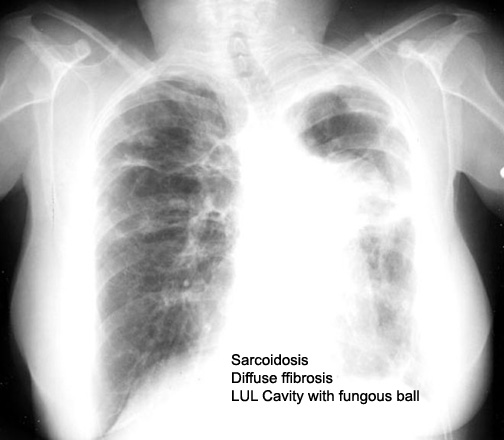

Labeled Image What are the pulmonary manifestations of Ankylosing spondylitis?